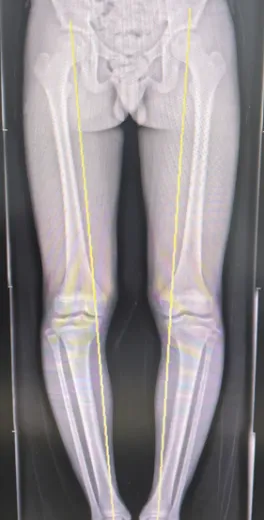

患者站立位力线

科室主任梁捷予接诊后,为小李进行了全面的检查和评估,很快揪出了问题的核心:小李的O型腿导致双下肢受力线严重偏移,走路、跑跳时的重量几乎全部压在膝盖内侧,长期的超负荷压力,不仅磨坏了关节内的半月板,还引发了一系列结构改变和疼痛症状。